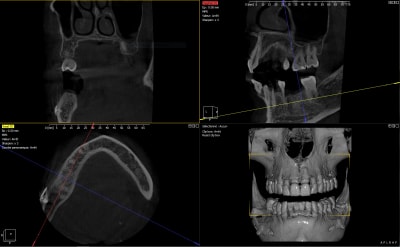

Le verdict ce matin au CBCT... Trop vestibulé (classique) même si mon axe d'émergence sort bien au niveau de la cuspide palatine maxillaire, sous forage et nécrose par compression en essayant de le tanker à la main. Dans du D1 vous avez une alternative cylindrique dans vos tiroirs ou vous restez sur du cylindro-conique ? Dépose programmée. Pour la pulpectomie de 47, je vais attendre un peu. 8 semaines vous semble raisonnable pour réimplanter ? Quels sont vos conseils pour la réintervention ? Merci à tous

clairement ton image de CBCT me fait plutôt penser à un pb d'échauffement

peut être en plus augmenté par la compression générée par le design de ton implant, très classique avec le CC parce que c'est pas un implant auto taraudant, il est fait pour être compressif...

Compression lors de la pose, c’est sûr. Trop vestibulaire, aussi. Échauffement lors du forage, en général la douleur est plus rapide, plutôt 2-3 jours après la pose.

En revanche, c’est l’énorme image apicale à l’implant qui m’étonne. Tu as le CBCT, préopératoire ?

Concernant le cbct post-op, l'examen clinique ne m'a clairement rien amené, à savoir :

- une douleur équivalente entre 47-46-45 en palpation majorée en regard de la plaque d'ostéosynthèse

- une percussion positive sur 47-45 et négative sur l'implant

- une vitalité positive sur 47 mais minorée vis à vis de celle de 45

- La rétro-alvéolaire ne m'a clairement apporté aucune information (peut-être n'est-elle pas assez qualitative)

Certes il y a une irradiation supplémentaire mais ce n'est pas dit que sans CBCT j'aurai envisagé la dépose dans un délai aussi bref.

Ma question, c'etait as-tu la meme image apicale sur le cbct preop que celle qu'on voit a l'apex de l'implant en post-op?

Ca m'etonnerait qu'elle se soit formee en 15 jours.